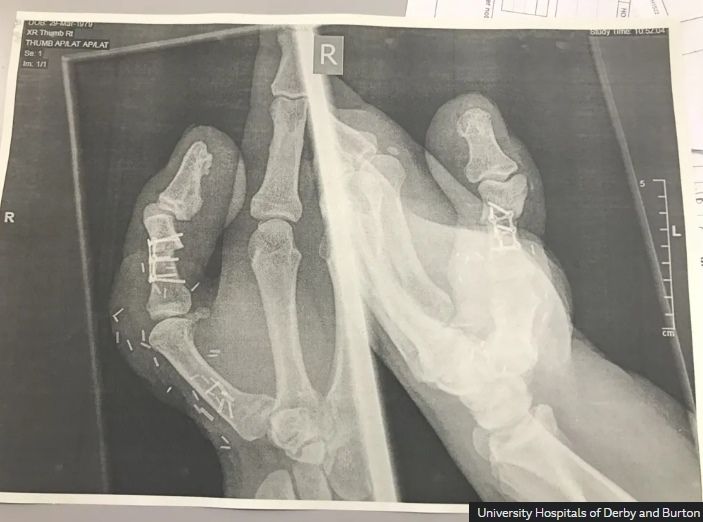

엄지발가락 성공적으로 이식받은 구두수선공 데이비드리. 출처=BBC

사고 직후 그는 인근 병원으로 옮겨졌고, 의료진은 여러 재건 수술 방법을 고심한 끝에 리의 오른발 엄지발가락을 절단해 잘려 나간 엄지에 붙이는 이식 수술을 진행했다.

발과 손을 동시에 수술하는 수술은 총 10시간가량 소요됐다. 수술은 성공적으로 끝났지만 회복 과정은 쉽지 않았다.